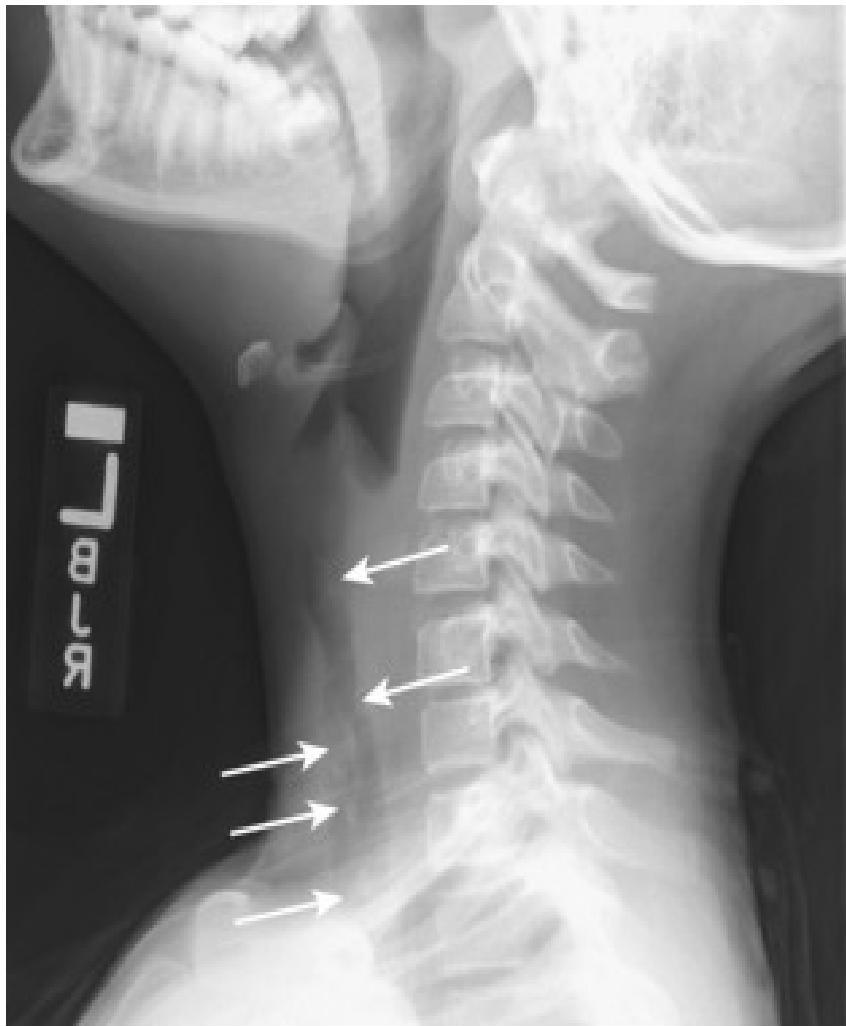

- Soft-tissue Lateral Neck Radiographs:

- Portable if possible.

- Positive in 80% of cases.

- Feature: An enlarged epiglottis protruding from the anterior wall of the hypopharynx (the “thumb sign”).

- Other findings: Thickened aryepiglottic folds, loss of vallecular air space, distended hypopharynx.